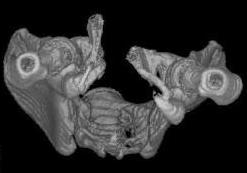

Уважаемые коллеги! Девушка 18л сросшиеся переломы лонных, седалищных костей с обеих сторон, перелом крестца справа,перелом костей голени справа (зио), 3 мес после травмы, АВФ снят с таза. Патологической подвижности нет. Стоит самостоятельно, ходит с костылями, поскольку 3 месяца практически не ходила. Беспокоит выступание лонной кости в области лобка, хотя объективно грубого косметического дефекта нет. На кт разворот лонной кости в сагиттальную плоскость. Вопрос: стоит ли добиватьсяполной репозиции или же достаточно произвести остеотомию верхушки выступающего отломка?

Предварительный диагноз- посттравматическая вертикальная нестабильная деформация таза II степени, неправильно срастающийся перелом боковой

массы крестца справа, правой лонной и седалищной костей, застарелый разрыв лонного сочленения.

Для уточнения диагноза ниеобходимы обзорные рентгенограммы таза (прямая и inlet), Кт срезы на уровне переломов для определения степени сращения и решения вопроса о методе оперативного восстановления анатомии (делать ли остеотомию, низводить ли задние отделы), ни о какой "остеотомии выступающих отломков" тем более у девочки 18 лет речи быть не может.

При более детальном распросе, наверное, удастся обнаружить и другие жалобы, либо они появятся при увеличении нагрузок. Как представляется, задачей лечения будет являться восстановление целостности и стабильности тазового кольца. Оптимальным вариантом может быть низведение левой половины таза, затем реконструкция передних отделов. Варианты выполнения репозиции и фиксации - тема отдельного разговора.